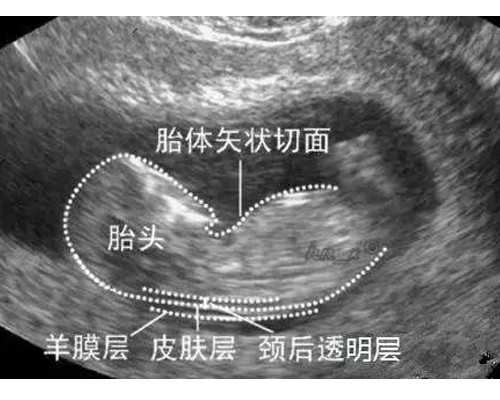

再者,医院的设备设施也是影响试管婴儿成功率的重要因素。先进的医疗设备可以提高检查的准确性、治疗的精准性以及胚胎培养的质量。例如,高分辨率的超声设备可以更清晰地观察卵巢和子宫的情况,为医生提供更准确的诊断依据;先进的胚胎培养系统可以提供更稳定的温度、湿度和气体环境,有利于胚胎的生长发育。患者在选择医院时,可以实地考察医院的设备设施,了解其是否具备开展试管婴儿技术所需的先进设备。